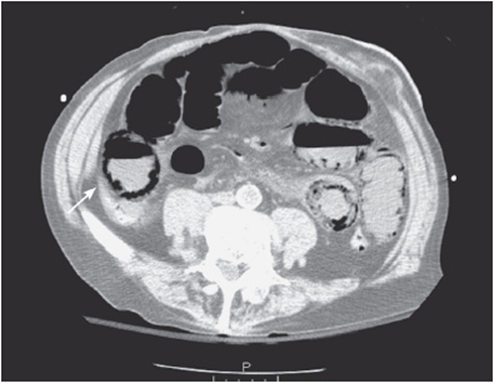

iii. Look for free fluid and intra-abdominal fluid collections:

• Free fluid in the abdomen is an abnormal finding and can be seen anywhere in the abdominal cavity (see Figure 56-3).

Figure 56-3. Free fluid.

• It most commonly represents blood, pus, ascites, or enteric contents.